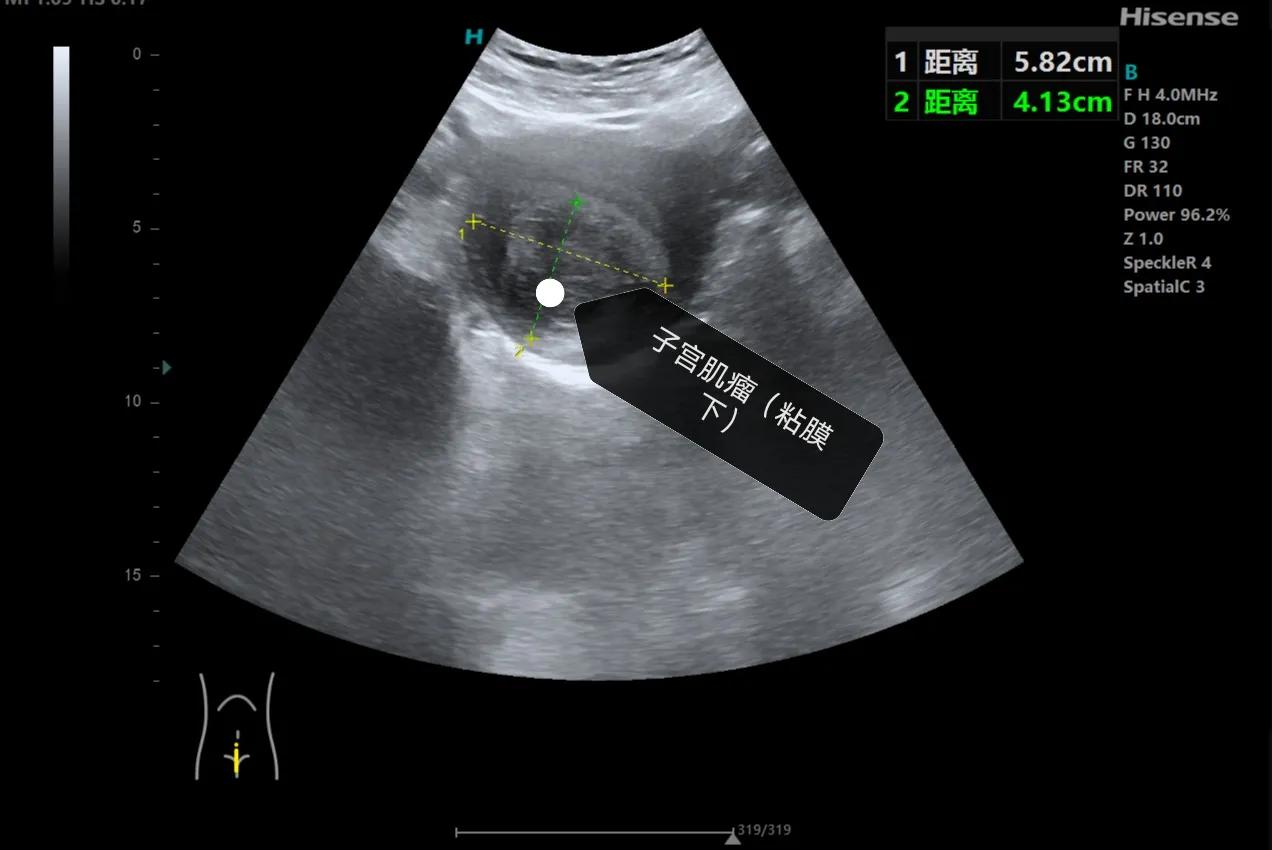

女性朋友关心的第二个问题“怎么确定自己有没有子宫肌瘤、肌瘤多大”,确定是不是患有子宫肌瘤很简单,做一个超声检查就可以了,下面我给大家分享一下子宫肌瘤的超声表现,子宫肌瘤根据位置分为粘膜下肌瘤、肌壁间肌瘤和浆膜层肌瘤,在超声上主要表现为低回声结节,边界比较清楚,小的肌瘤一般形态规则,呈椭圆形,大的肌瘤形态可表现为欠规则,呈分叶状,肌瘤周边一般可见环状的血流信号。

粘膜下肌瘤